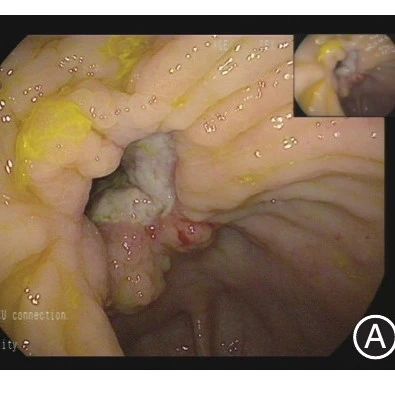

病例│肠型白塞病伴肠穿孔一例